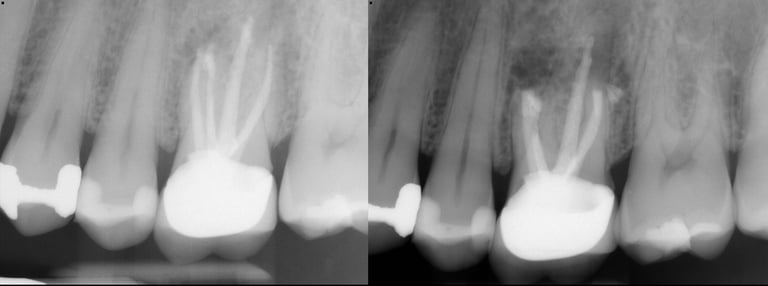

Gallery 4: Healed Cases

Completely healed cases is what matters most. The lesion/infection (black circle) heals in with bone over time.